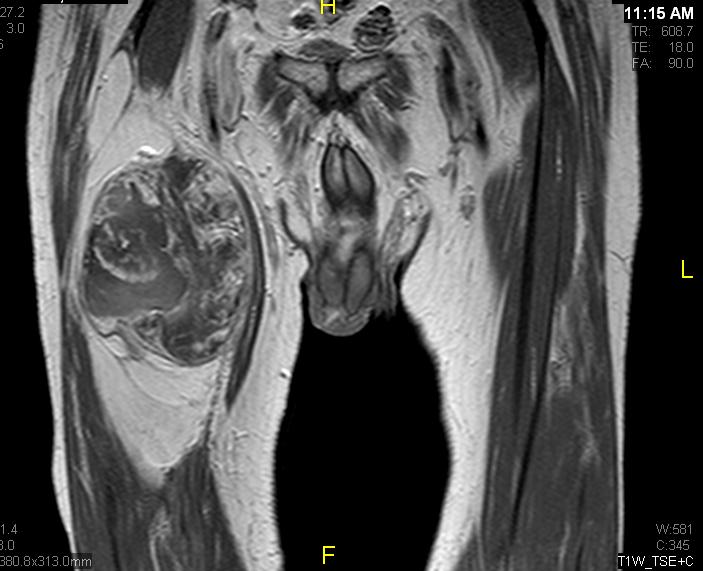

Fig. 7 & 8 Magnetic Resonance Image shows a large heterogeneous mass in the right thigh with low intensity signal on Axial (Fig. 7) and Coronal (Fig. 8) T1-weighted images admixed with high signal areas. The high signal areas represent low grade fatty tissue and low signal the dedifferentiated areas. Higher intensity signal is visible compatible with hemorrhage or necrotic tissue.

Fig. 9 Coronal fat suppressed T1-weigthed MR image demonstrates a large heterogeneous mass in the anterior compartment of the thigh with some areas suppressed corresponding with fatty areas within the tumor. Central hyper enhanced areas compatible with hemorrhage or necrosis.